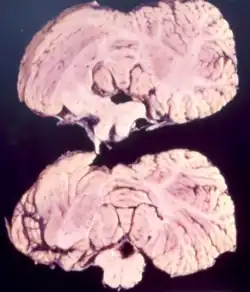

Studies from kuru infected individuals have revealed information explaining the effects that the disease can have on the brain. In the early stages of the disease, infected individuals may experience withdrawal, incoordination, tremors, and curling of the toes and feet.[17] To understand these difficulties in balance and coordination, studies were conducted to analyze the brain of kuru infected individuals. These studies by Klatzo et al., found that neurons in a kuru infected brain were abnormally small and lighter in color compared to their healthy counterparts.[17] Affected neurons appear "moth-eaten" due to their characteristic deformations. [17] These abnormalities in the neurons of the brain infected by kuru were similar to those with Creutzfeldt-Jakob disease (CJD).[17]